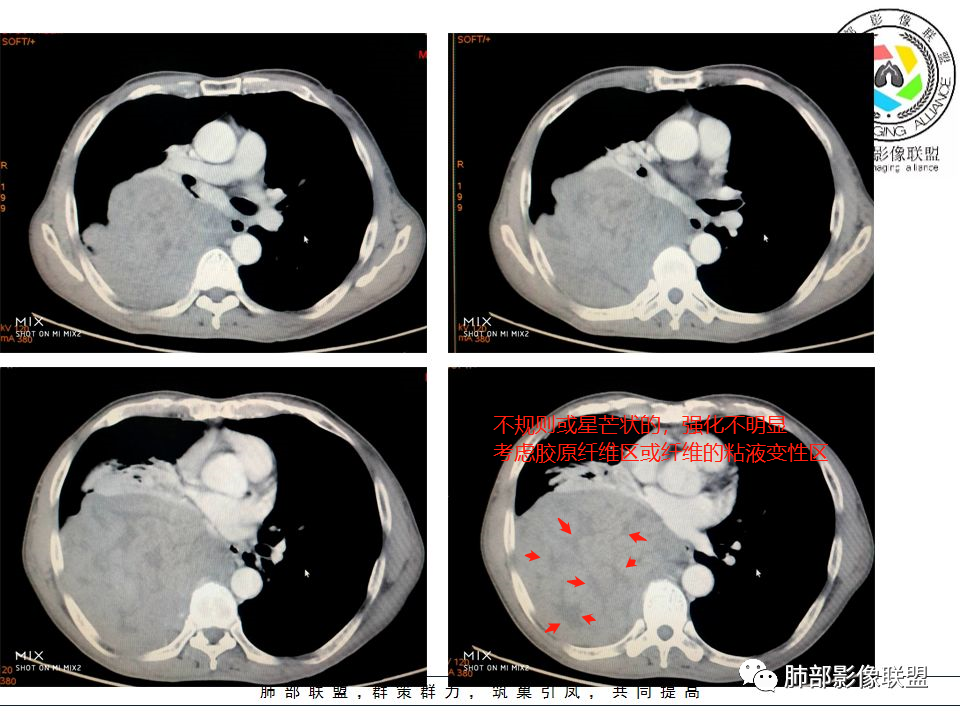

3)CT平扫肿瘤多呈等或稍低密度;肿瘤较小者密度均匀,较大者内部密度常不均匀、见多发灶性或不规则星芒状中心低密度区(细胞稀疏区含有丰富胶原纤维易发生黏液样变性或囊性变),钙化少见。

胸膜孤立性纤维瘤的星芒状瘢痕

5)肿瘤的强化程度及方式:增强扫描肿瘤早期实性成分呈不均匀斑片或斑驳样强化,多呈“ 地图样” 明显强化,强化程度不一,可呈轻度-显著强化,静脉期持续强化,多期增强及动态增强扫描均呈“快进慢出”型强化,且强化范围逐渐增大并趋均匀。肿瘤由肺动脉或支气管动脉供血,内部及周围常见多发粗细不等强化或流空肿瘤血管影,呈蛇纹血管征。

胸膜孤立性纤维瘤的蛇纹血管征

定位:肿块长轴与胸膜平行,宽基底与胸膜相连,两端可见胸膜尾征,附近血管、支气管被推移,提示肺外胸膜起源;

定性:边缘光滑,浅分叶,边缘膨隆,提示肿瘤可能大,非炎性病变;

肿块动脉期明显不均匀强化,渐进性强化,呈“快进慢出”,其内可见小片、星芒状低密度区,提示胶原纤维或粘液变性区,首选胸膜来源孤立性纤维瘤,本例未见明显蛇纹血管征。